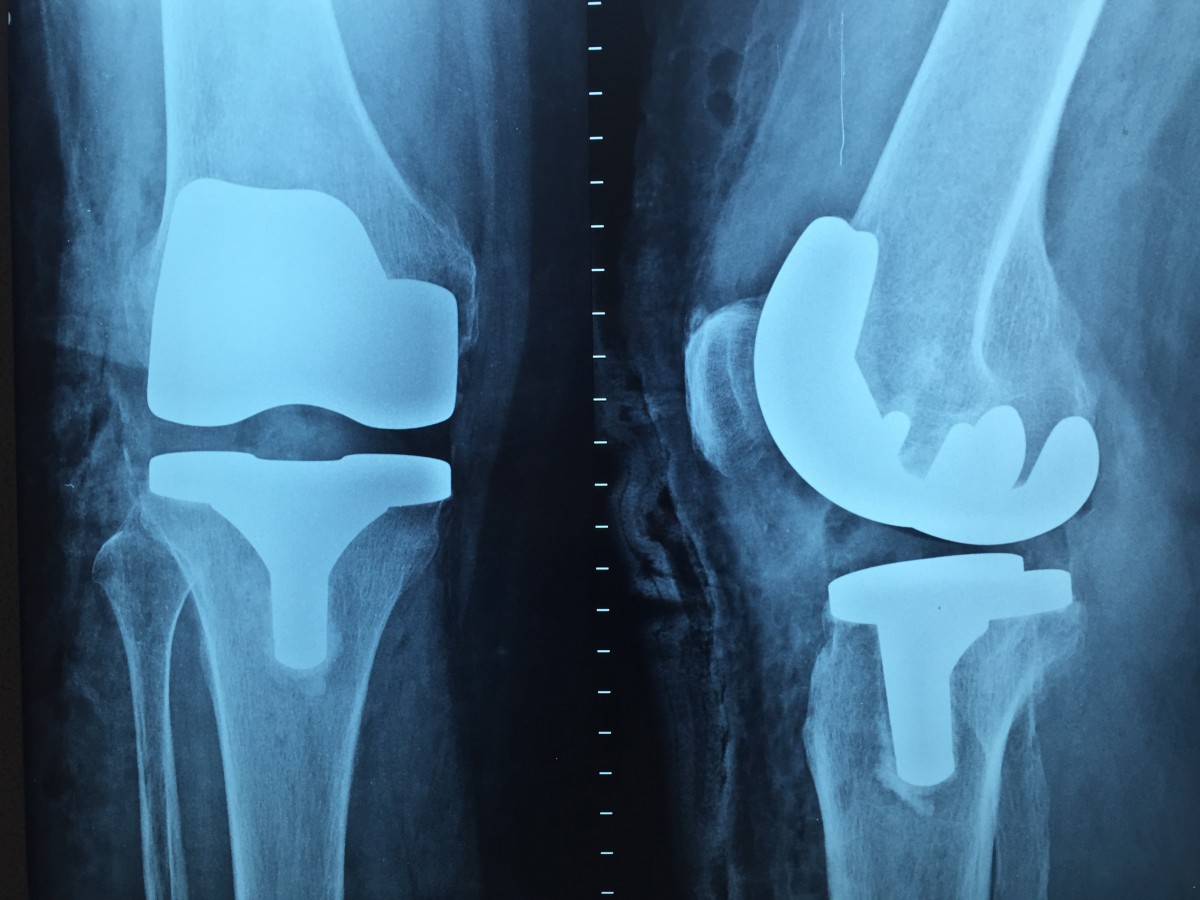

환자를 급히 서울 병원으로 모시고 와 각종 정밀검사를 진행했다. 예상대로 무릎 인공관절을 해야만 하는 심각한 관절염 말기였다. 문제는 이 정도로 관절염이 심하면 가장 최후의 치료방법인 무릎 인공관절술을 진행하더라도 수술 결과가 좋지 않을 수 있다. 환자는 이미 10여 년 전 허리 고정술(나사못 고정술)을 받은 병력이 있었다. 허리 고정술을 받게 되면 수술 부위를 잘 움직이지 못하기 때문에 허리 주변 근육이 상당히 굳게 된다. 이뿐만 아니라 허리와 밀접한 연관을 지닌 무릎 근육도 굳고 말라버린다. 이런 경우 통증 치료보다도 우선돼야 할 것이 근육을 강화하는 치료다. 수술 전 무릎 주변의 근육을 강화하는 치료가 매우 중요한데, 아이러니하게도 환자와 같은 환자들은 극심한 통증 때문에 움직이기가 힘들어 운동 치료에 어려움을 겪는다.

따라서 수술 전 환자에게 근육의 이완과 수축을 해주는 신경근 자극기를 하루 2~3회 사용토록 했다. 이후 근력이 어느 정도 향상된 후 양쪽 무릎에 인공관절 치환술을 진행했다. 인공관절 치환술이란 손상된 관절을 금속 재질의 인공관절로 바꿔 운동기능을 회복시키고 통증을 없애는 수술이다. 수술 후에도 상태가 어느 정도 회복돼 운동 치료가 가능해질 때까지 환자에게 계속 저주파 자극을 줘 근육과 인대를 강화했다. 여기에 관절의 운동범위를 증가시키는 각종 운동치료를 병행하며 서서히 운동량을 늘려나갔다.

그 결과 환자의 무릎 인공관절 술은 성공적이었다. 수술 후 하루가 다르게 회복돼 관절의 운동범위가 늘어났으며 다리에 힘이 들어갔다. 하지만 수술 후 당장 경과가 좋다고 해 방심하고 재활, 관리에 소홀해선 안된다. 환자에게 앞으로도 될 수 있으면 바닥 생활을 피하고 의자를 사용하며, 관절 주변의 근육이 굳거나 마르지 않도록 근육을 자극하고 강화해야 한다고 당부했다. 이것만 주의하면 환자가 현재의 인공관절을 내 무릎처럼 20년가량 사용하는 데에 큰 무리가 없을 것이다.